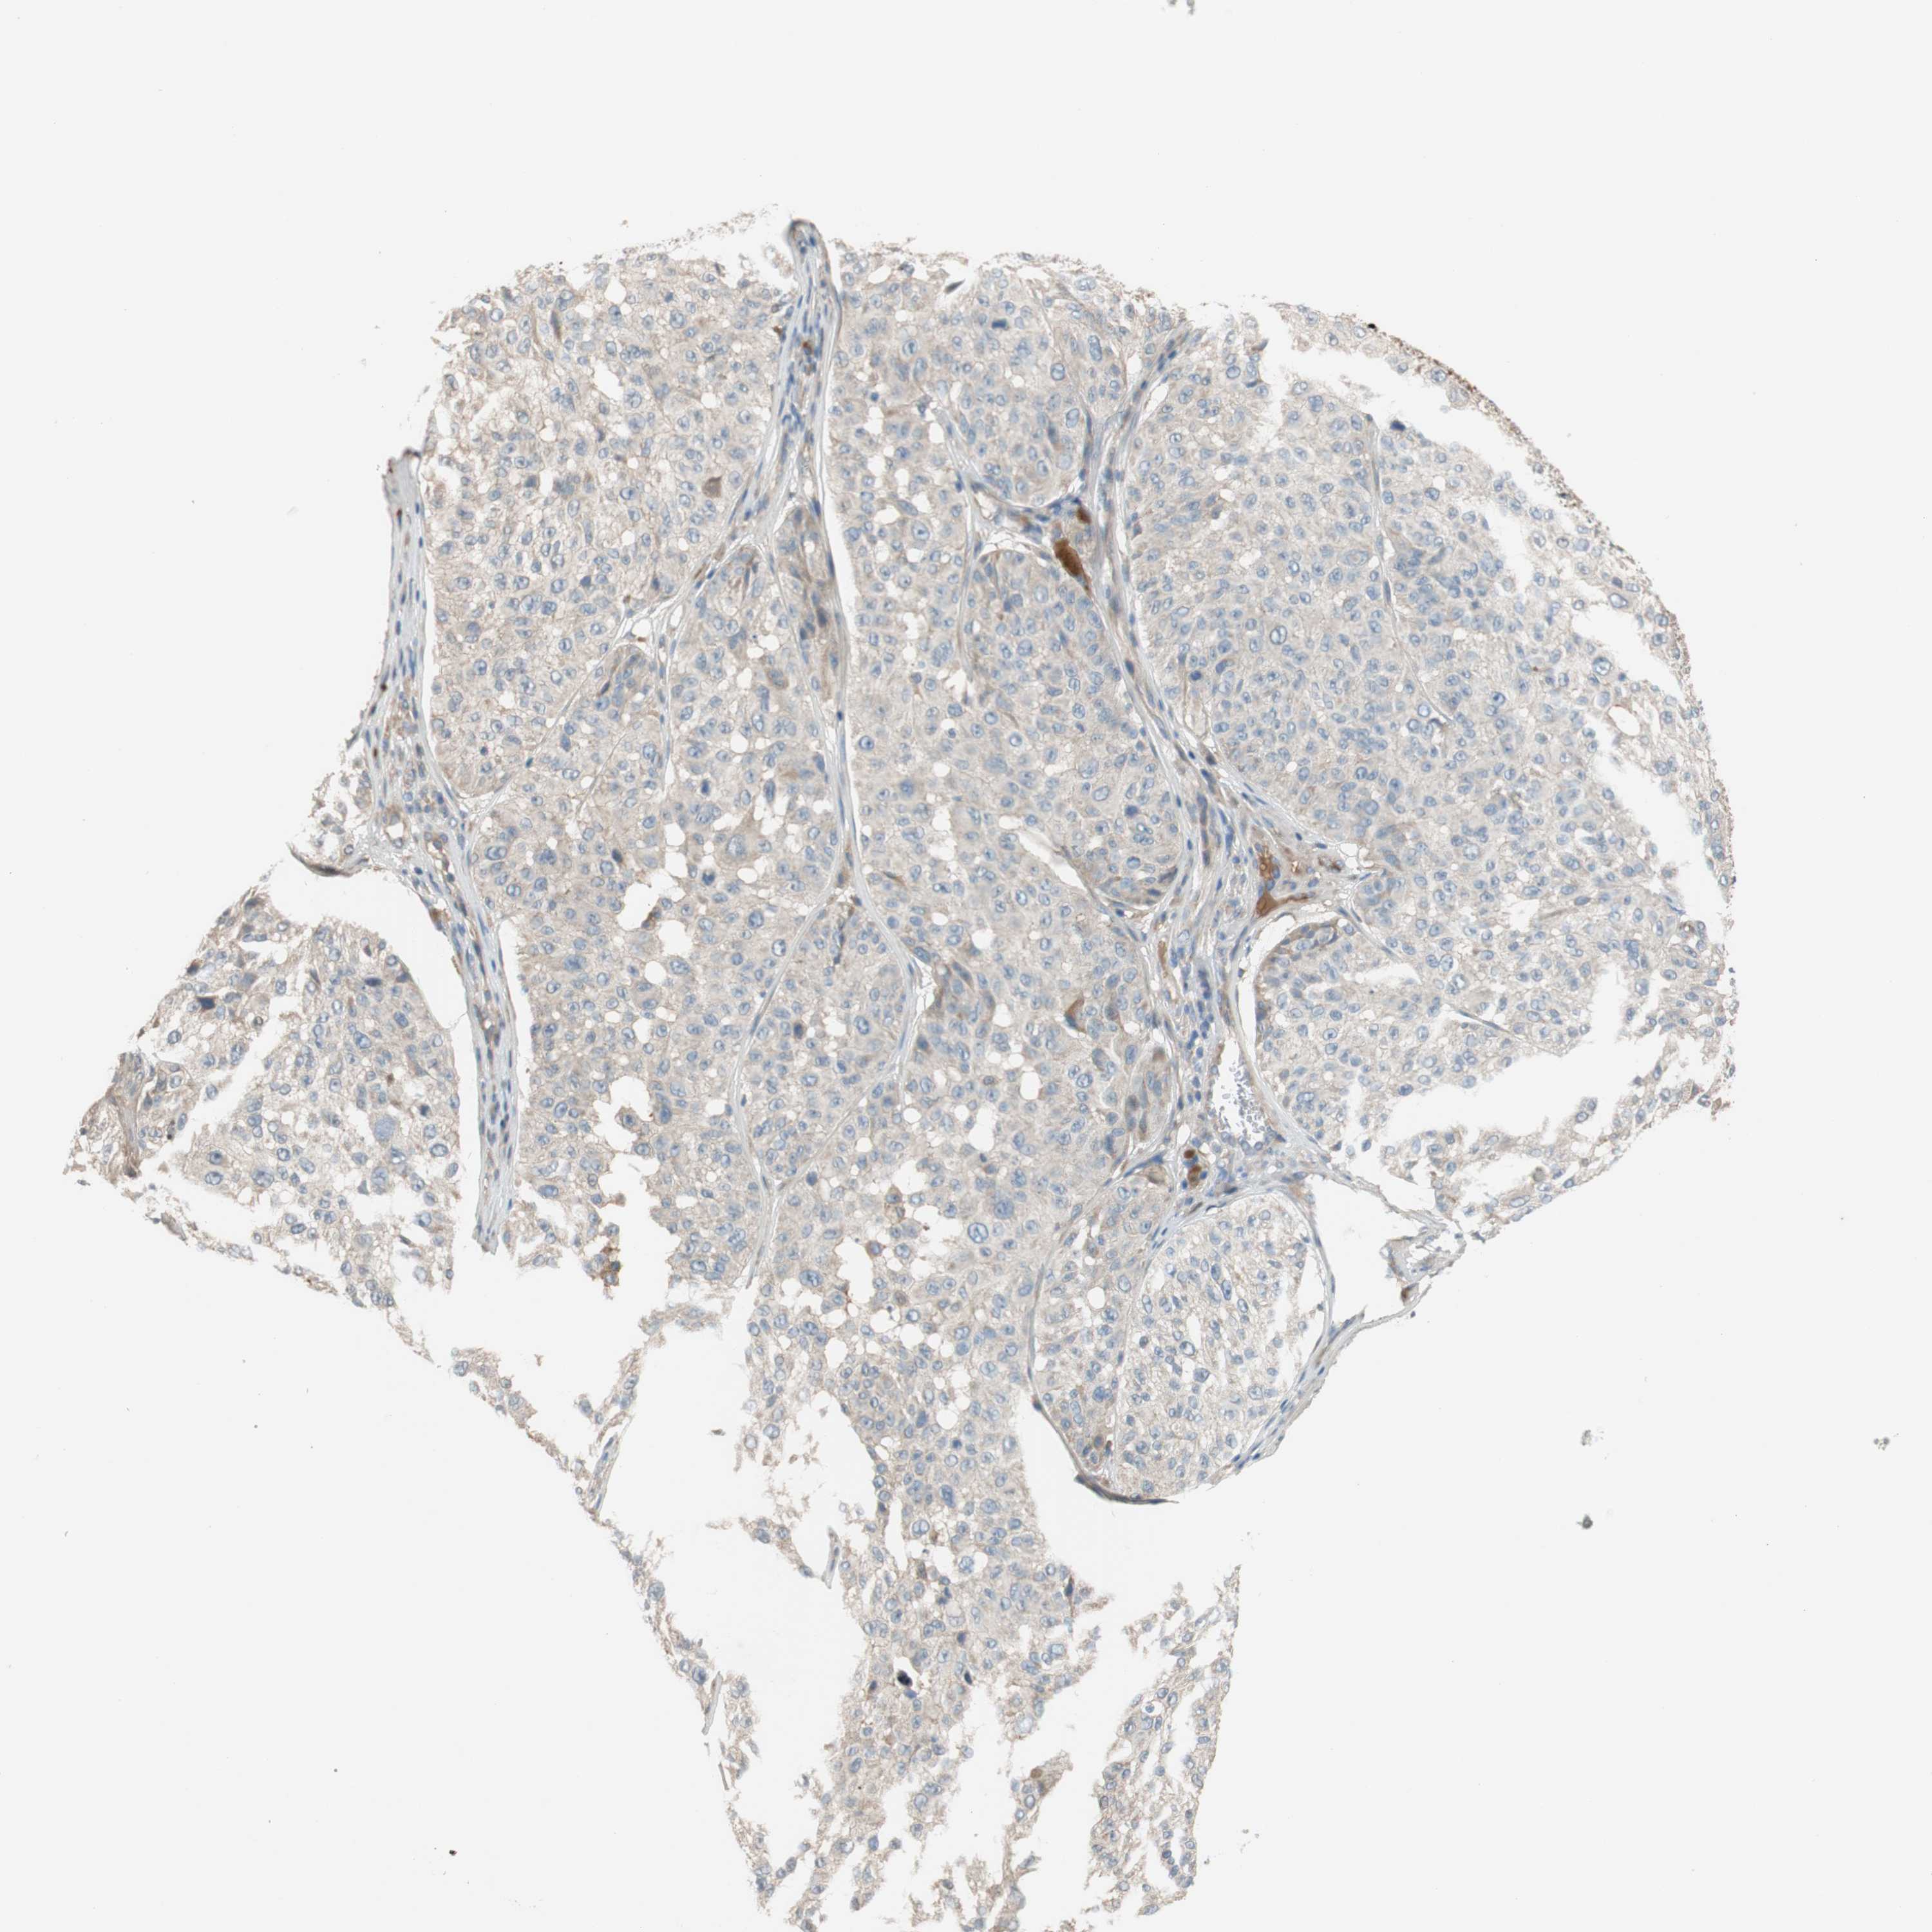

MELANOMA - Protein expressioni

A mouse-over function shows sample information and annotation data. Click on an image to view it in a full screen mode. Samples can be filtered based on level of antibody staining by selecting one or several of the following categories: high, medium, low and not detected. The assay and annotation is described here.

Note that samples used for immunohistochemistry by the Human Protein Atlas do not correspond to samples in the TCGA dataset.

Antibody stainingi

Antibody staining in the annotated cell types in the current human tissue is reported as not detected, low, medium, or high, based on conventional immunohistochemistry profiling in selected tissues. This score is based on the combination of the staining intensity and fraction of stained cells.

Each image is clickable and will lead to virtual microscopy that enables deeper exploration of all samples and also displays staining intensity scores, fraction scores and subcellular localization as well as patient and tissue information for each sample.

Malignant melanoma, NOS

Malignant melanoma, Metastatic site